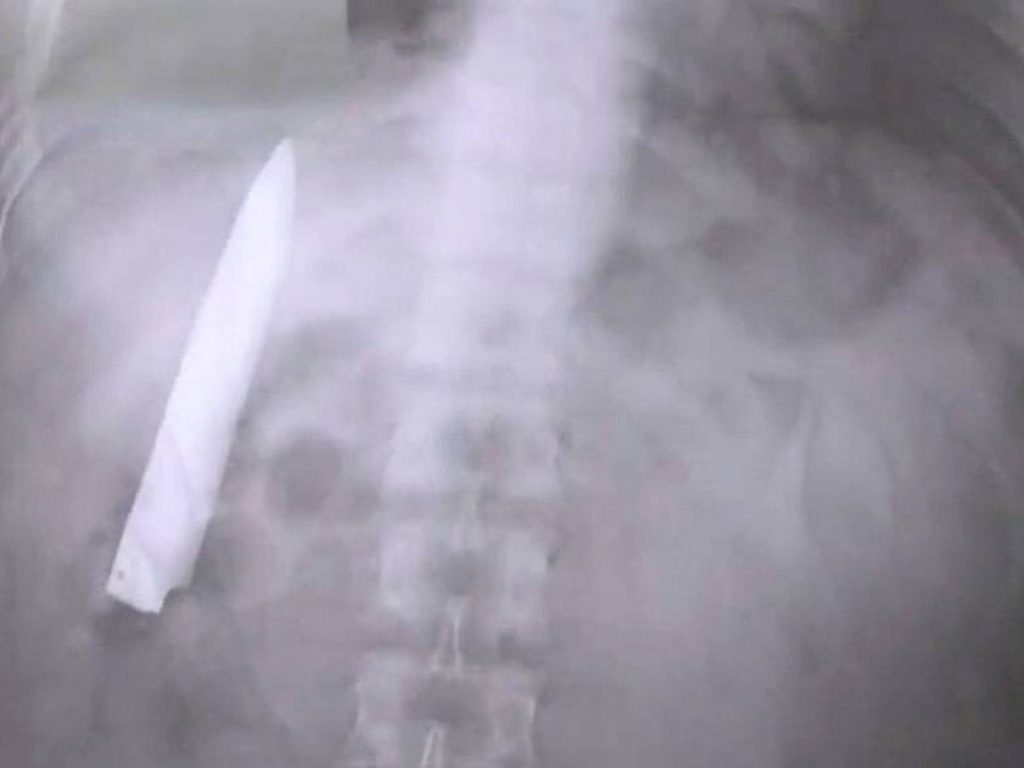

La sorpresa fue mayúscula para los especialistas. Tras realizar radiografías, descubrieron que el hombre, de 44 años, tenía un cuchillo incrustado en el pecho. Al ser consultado sobre el hallazgo, el paciente confesó que el objeto se había alojado en su cuerpo tras un violento altercado ocurrido hacía aproximadamente diez años.

Los médicos locales detallaron que las radiografías revelaron que el cuchillo se había hundido en el omóplato derecho del paciente, milagrosamente esquivando cualquier órgano vital. Ante este hallazgo, los cirujanos procedieron a una delicada operación para extraer el cuchillo.